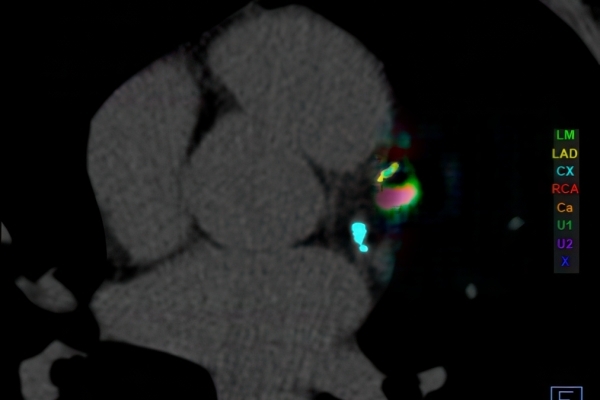

• Kardiovaskuläre Bildgebung (MRT- und CT-Untersuchungen des Herzen)

• Gefäßdiagnostik (CT-Angiographie)

Im Zentrum all meiner Bemühungen steht stets der Mensch. Mich motiviert am Beruf besonders die detektivische Spurensuche durch einen nicht-invasiven Blick in den menschlichen Körper. Radiologische Einschätzungen sind entscheidend für eine korrekte Diagnose und die Wahl der Therapie durch die behandelnden Ärzte.

Wir bieten ein breites Spektrum an Untersuchungen an, von Standarduntersuchungen der Gelenke, Organe oder großflächigen Körperregionen bis zu Spezialuntersuchungen zum Beispiel des Herzen oder der Gefäße. Zusätzlich werden Angiographien (Darstellung von Blutgefäßen), Endometriose-Abklärungen und Mamma-Untersuchungen durchgeführt. Genauere Details können Sie der MRT/CT-Übersicht und der Preisliste entnehmen, oder Sie wenden sich direkt an unser Team, das Sie gerne zur passenden Untersuchung berät.